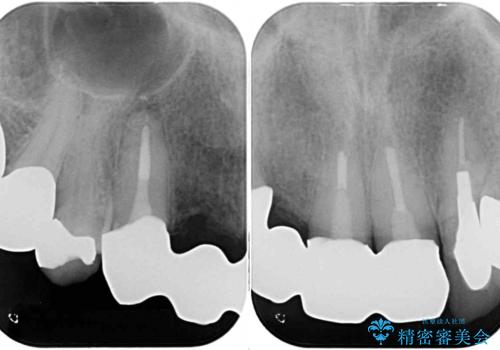

- 前歯のブリッジのセラミックが欠けてしまい、作り直したいとのことで来院された患者様です。

犬歯はブリッジの中で虫歯が進行していたため、根管治療からやり直しをした後、オールセラミックブリッジにて補綴することとしました。